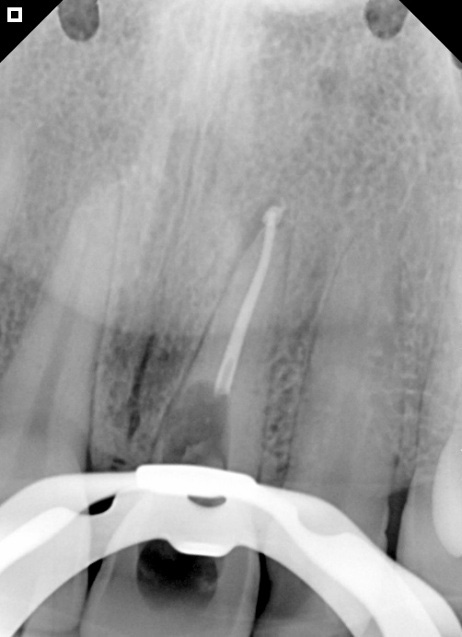

Patient I.N.A.A., 29 years old, female, came to the Escola De Ensino Educação Inteligente (EI Uningá – Londrina, Paraná) after being treated at a private clinic. The patient reported that a routine radiographic examination was performed, and the dentist identified a periapical lesion in tooth 11, in addition to darkening of its color. Endodontic treatment of the tooth was then proposed. At the same location, an attempt was made to access the pulp, but without success. She was referred for a CT scan (Figures 1A and 1B).

Figure 1: Tomographic image, coronal section (A)

Figure 2: Perforation